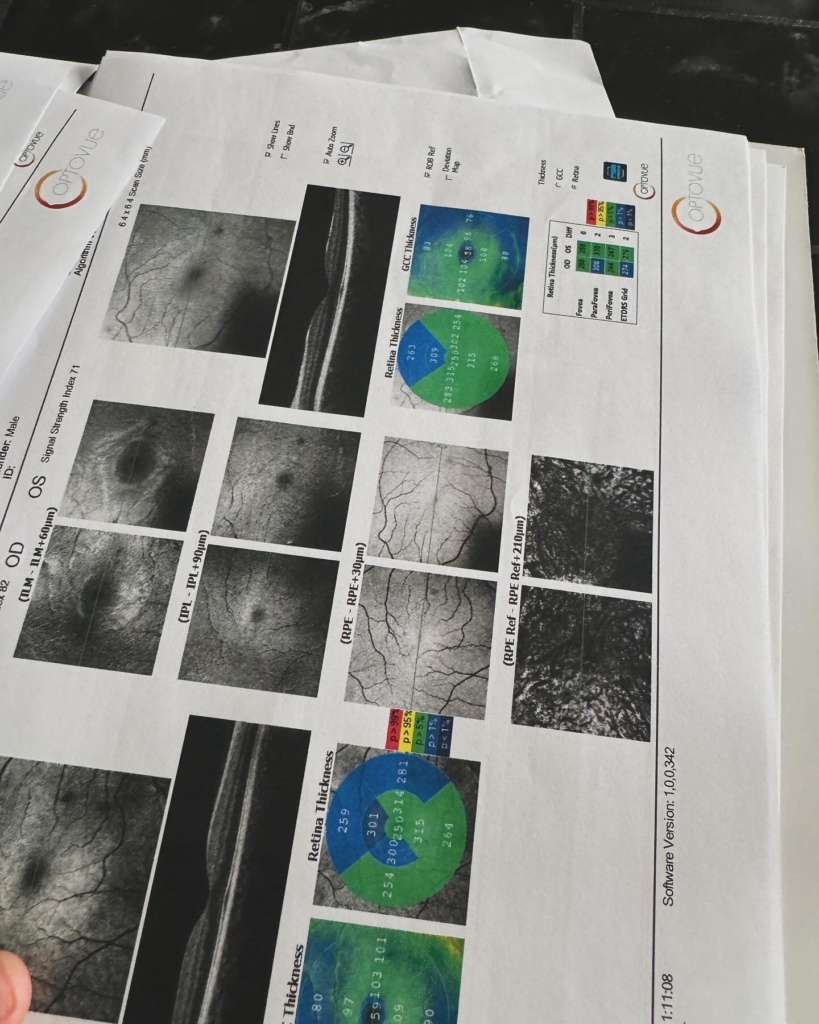

Ή μάλλον για τον τύπο που λέγεται Μάστορας. Ακούω κατά καιρούς διάφορες φήμες και έτυχε να ακούσω και τώρα κάποιες άλλες που δεν τιμούν οποίους τις διαδίδουν οπότε θα ανεβάσω μερικές φωτογραφίες από τις δύο δύσκολες τελευταίες εβδομάδες. Ο πιο σημαντικός λόγος που τις ανεβάζω είναι όμως για να μοιραστώ την ιστορία μου για την αμφοτερόπλευρη δακρυοαδενίτιδα.

Αιτία ο κοβιντ ο άτιμος… Ψάξτε το. Μπορεί και κάποιος από εσάς να υποφέρει από αυτήν αυτό τον καιρό και να μην ξέρει πώς να το διαχειριστεί.. Εγώ μπήκα στο νοσοκομείο και είχα την πιο απίστευτη γιατρό την Δήμητρα Π. να με προσέχει σε κάθε βήμα. Είμαι καλά τώρα όποτε πάμε γερά!», έγραψε χαρακτηριστικά ο Χρήστος Μάστορας.